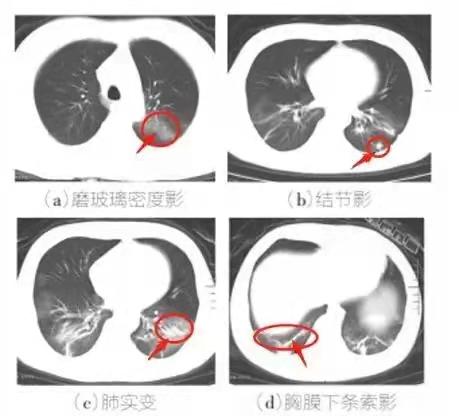

2.胸部CT特征:多发磨玻璃影、斑片影及实变影。

新冠病毒无症状感染者指呼吸道等标本新型冠状病毒病原学检测呈阳性,无相关临床表现,如发热、干咳、咽痛等可自我感知或可临床识别的症状与体征,且CT影像学无新冠肺炎影像学特征者。